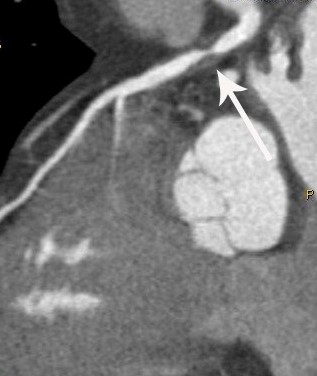

冠脉CTA属于是无创性评价冠状动脉解剖结构的影像学方法。只需借助静脉注入对比剂(含碘造影剂),利用先进的CT扫描和后处理技术,可对心脏进行三维重建和对冠状动脉及其分支进行曲面拉直重建直观显示各个分支全程,并可对冠状动脉粥样硬化进行钙化积分扫描,使之成为一种简单有效而无创伤的冠状动脉疾病的早期诊断方法之一。其结果可用于分析和评价冠状动脉狭窄、冠状动脉粥样硬化斑块、冠状动脉慢性闭塞病变,也可作冠状动脉支架植入术后、冠状动脉旁路移植术后的CTA评价。

冠状动脉CTA